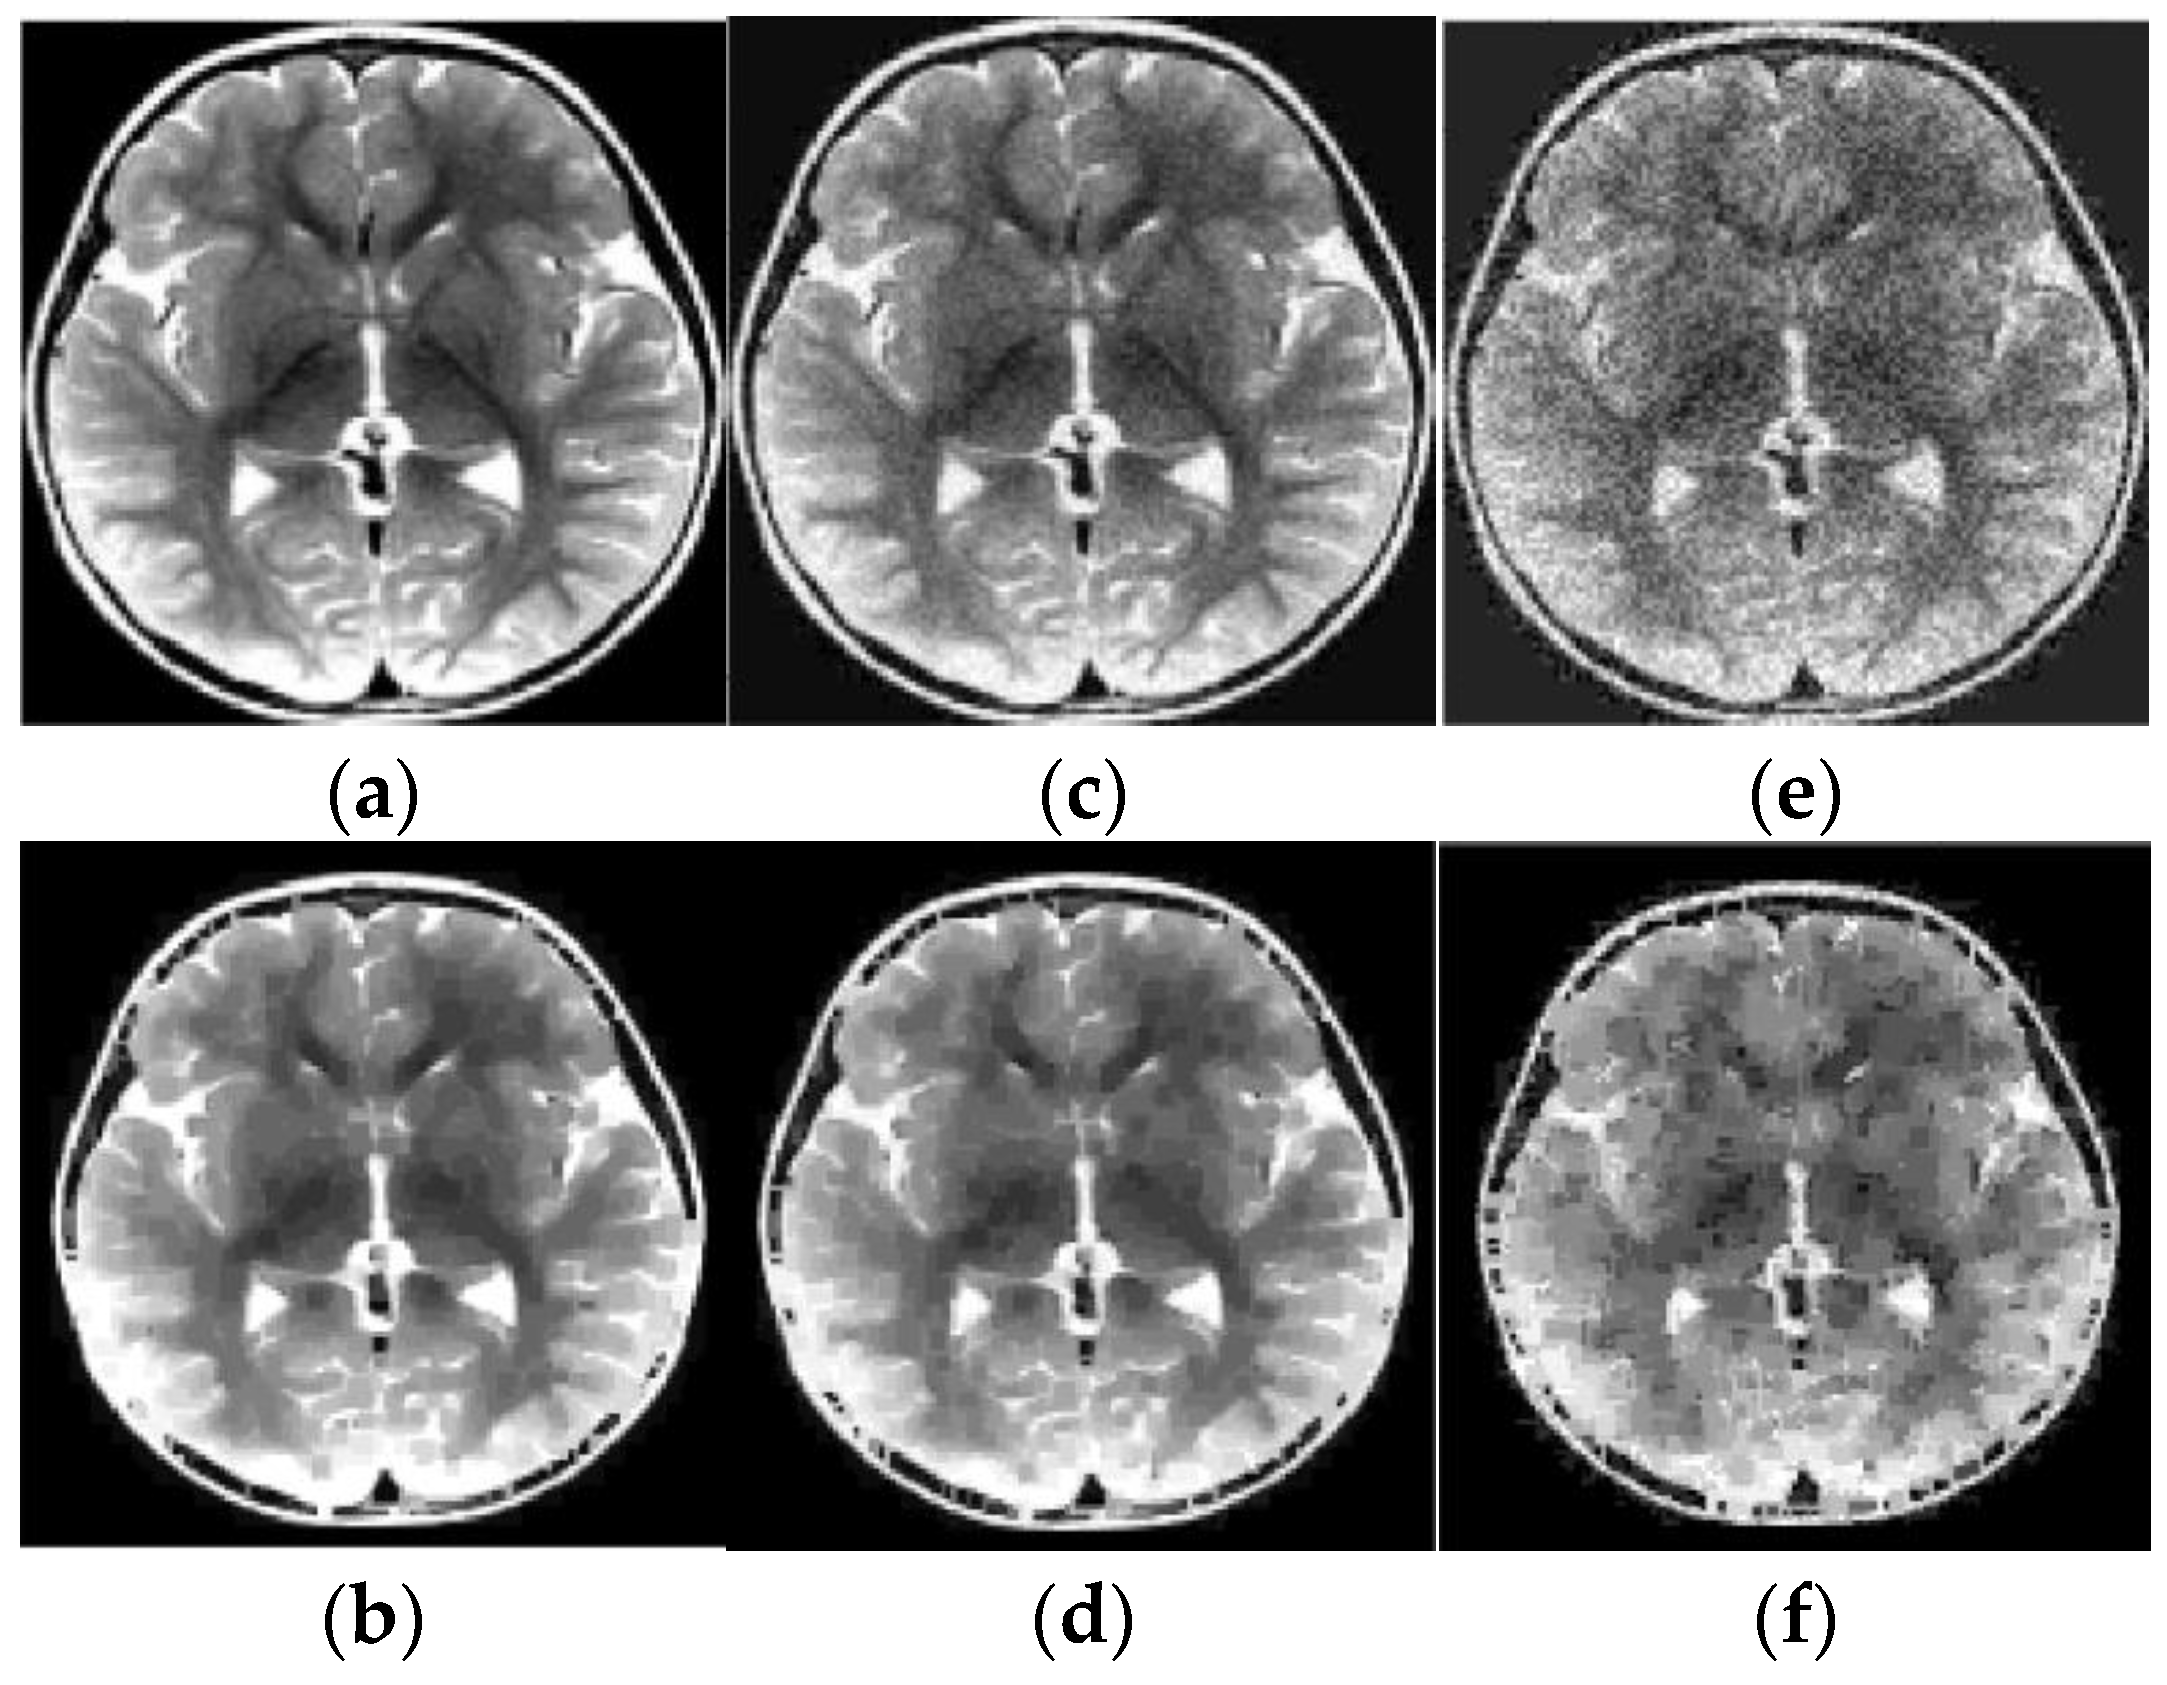

4.3. Inverse Radon Image Reconstruction